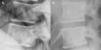

En los estudios radiológicos, además de la marcada esclerosis ósea, llamaba la atención, en la columna, la presencia de líneas paralelas a la cortical de los cuerpos vertebrales que daban lugar a la imagen de un pequeña copia del cuerpo vertebral en su interior, el denominado signo del «hueso dentro de hueso» (figs. 1-3). Este signo era evidente en varios cuerpos vertebrales. No presentaba deformidades morfométricas vertebrales ni calcificación de los ligamentos paraespinales.